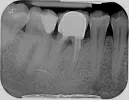

Согласно данному снимку видно, что имеется резорбция и убыль костной ткани до бифуркации, но состояние корней в области апекса неплохое. Поэтому рекомендуем обратиться к стоматологу - пародонтологу для клинического осмотра. Если пародонтологу удастся добиться стабилизации процесса, то возможно будет провести повторное перелечивание корневых каналов. Постановку штифта и коронки, если согласно заключению пародонтолога спасти зуб не удастся, то тогда удалять и устанавливать имплант.